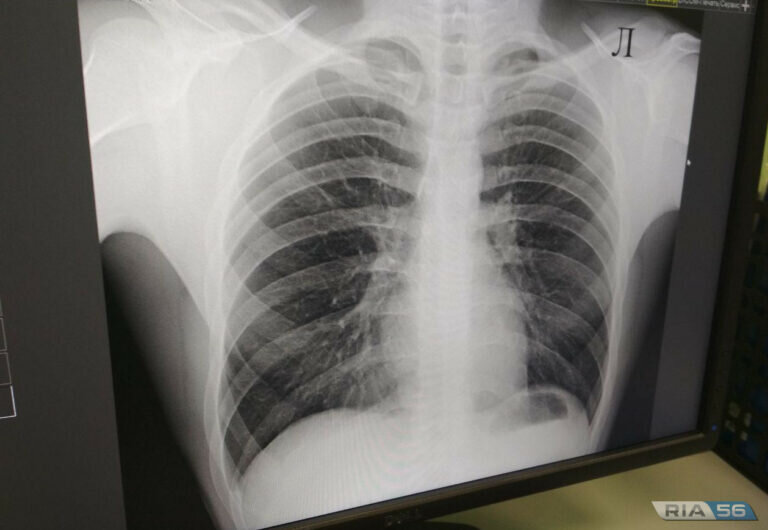

Несмотря на общеизвестный факт о курении как факторе риска развития рака лёгкого, большинство людей недооценивают вклад курения в увеличение статистики онкологических заболеваний.

На самом деле курение является доказанным фактором риска развития 13 видов онкологических заболеваний:

-лёгких